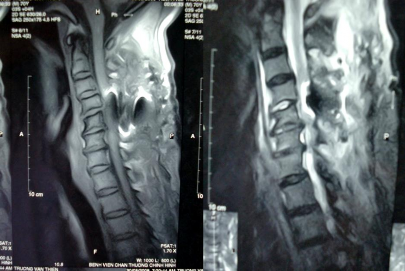

TRƯỚC MỔ (9 – 4 – 2008) HÌNH NGHIÊNG

(Trật 2 MK C4-C5/ CSC thoái hóa)

HÌNH CHÉO ¾

(Trật 2 mỏm khớp C4-C5)

SAU M

Trật mỏm khớp bên P – trật mỏm khớp bên T.

SAU MỔ (27 - 5 – 2008)

(Nắn vào tốt, cố định tốt)

HÌNH THẲNG HÌNH NGHIÊNG

MRI SAU MỔ: không thấy thoát vị đĩa đệm, nghi ngờ có phù nề tủy và chèn ép phía sau, do hình bị nhiễu nên không rõ.